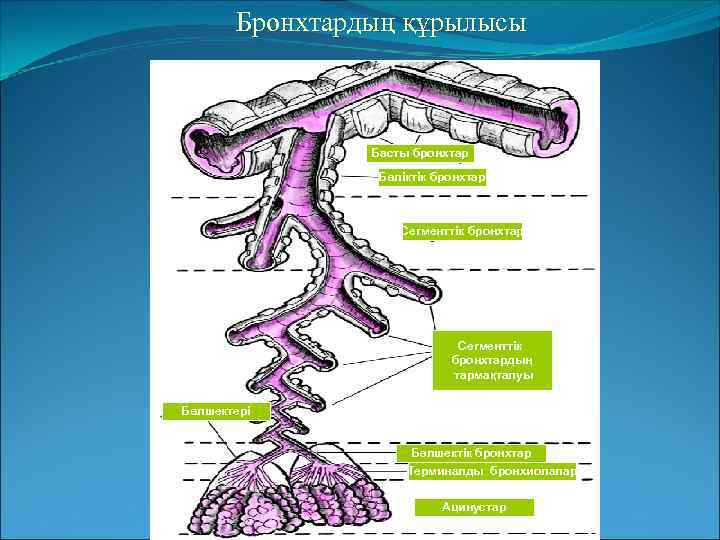

Электрондық микроскоппен түсірілген бронхтың кілегей қабаты